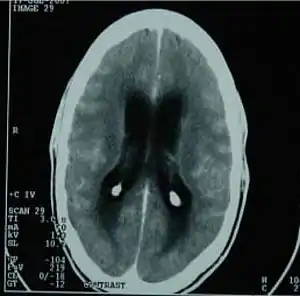

![]() | |

| CT scan showing tuberculous meningitis | |